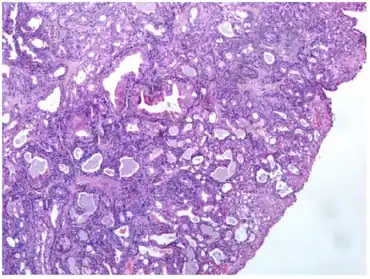

Tumor is made of tubular and cystic structures

All of the tumors are unencapsulated, but are usually well defined or circumscribed. The overlying surface epithelium is not involved. The tumor shows a dual or biphasic appearance, with glandular or cystic spaces showing inner luminal secretory cells with abundant granular, eosinophilic cytoplasm subtended by basal, myoepithelial cells at the periphery, adjacent to the basement membrane. The luminal cells will often have decapitation (apocrine) secretions and will also have yellow-brown, ceroid, lipofuscin-like (cerumen) pigment granules. There is no pleomorphic, limited mitoses, and no necrosis.[2]